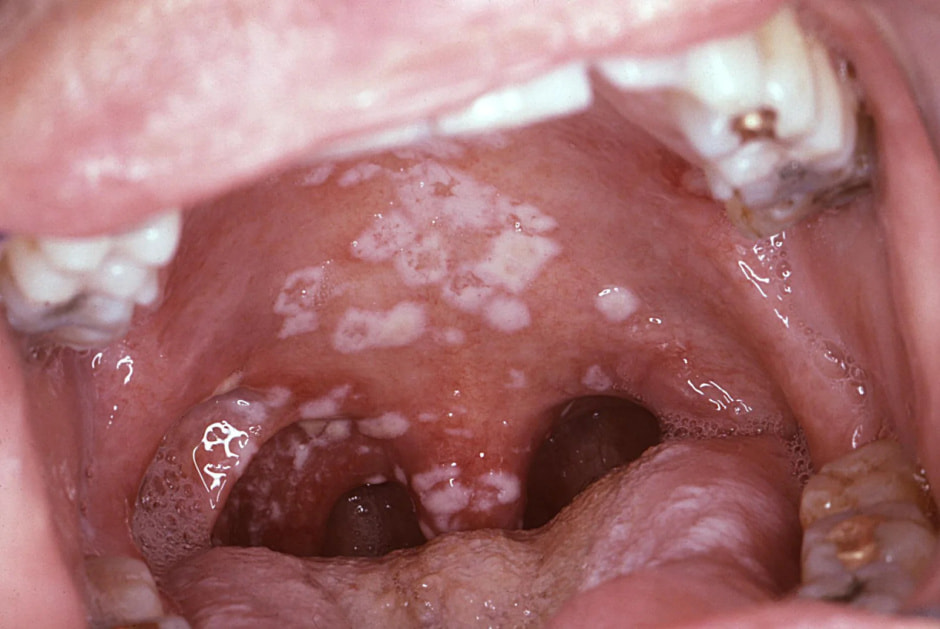

Налет на миндалинах или задней стенке глотки

Это может сигнализировать о развитии бактериального тонзиллита – ангины. Особенно, если у человека высокая температура до 38-39℃, которая почти не сбивается жаропонижающими. При этом кашля и насморка нет. В таком случае местными средствами не обойтись – нужно принимать антибиотики, назначаемые врачом.

боль_в_горле4.jpgТак выглядит горло при ангине (источник: wikipedia.org)

Также белый или желтоватый налет в горле может указывать на инфекционный мононуклеоз, который вызывает вирус герпеса 4-го типа (Эпштейна-Барра).

Если же налет имеет творожистую структуру, то он, вероятнее всего, вызван грибком (чаще всего рода Candida – возбудителем молочницы).

– Называется такое заболевание фарингомикоз. Оно проявляется белым творожистым налетом на задней стенке глотки, небных дужках и языке, першением и неярко выраженной болью в горле. Температура тела обычно остается нормальной или повышается незначительно.

боль_в_горле2.jpgТакой творожистый налет характерен для грибкового поражения (источник: sideeffectsupport.com)

Понять, что стало причиной налета в горле – ангина, фарингомикоз, мононуклеоз, может только доктор. Поэтому при возникновении такого симптома Мария Лобачева советует показаться врачу.